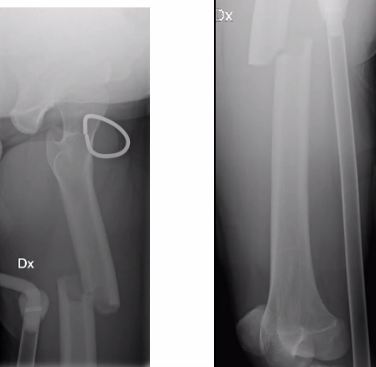

Q

65-årig kvinna

• Rökare, möjlig alkoholöverkonsumtion

• Tidigare kons beh distal radiusfraktur

• Ramlat över mattkant

• Sluten skada. NV intakt

Vad göra?

A

Plattan bra för att styra rotationskrafter, men direkt benläkning i radius och callusläkning i ulna